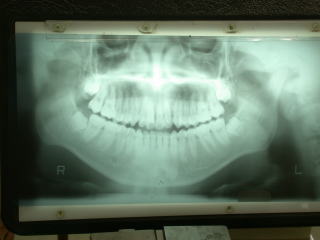

パノラマレントゲン 歯科用デンタルレントゲン

レントゲン検査により、歯根の湾曲や長さ等を把握し、抜歯可能と判断し、即日抜歯しました。